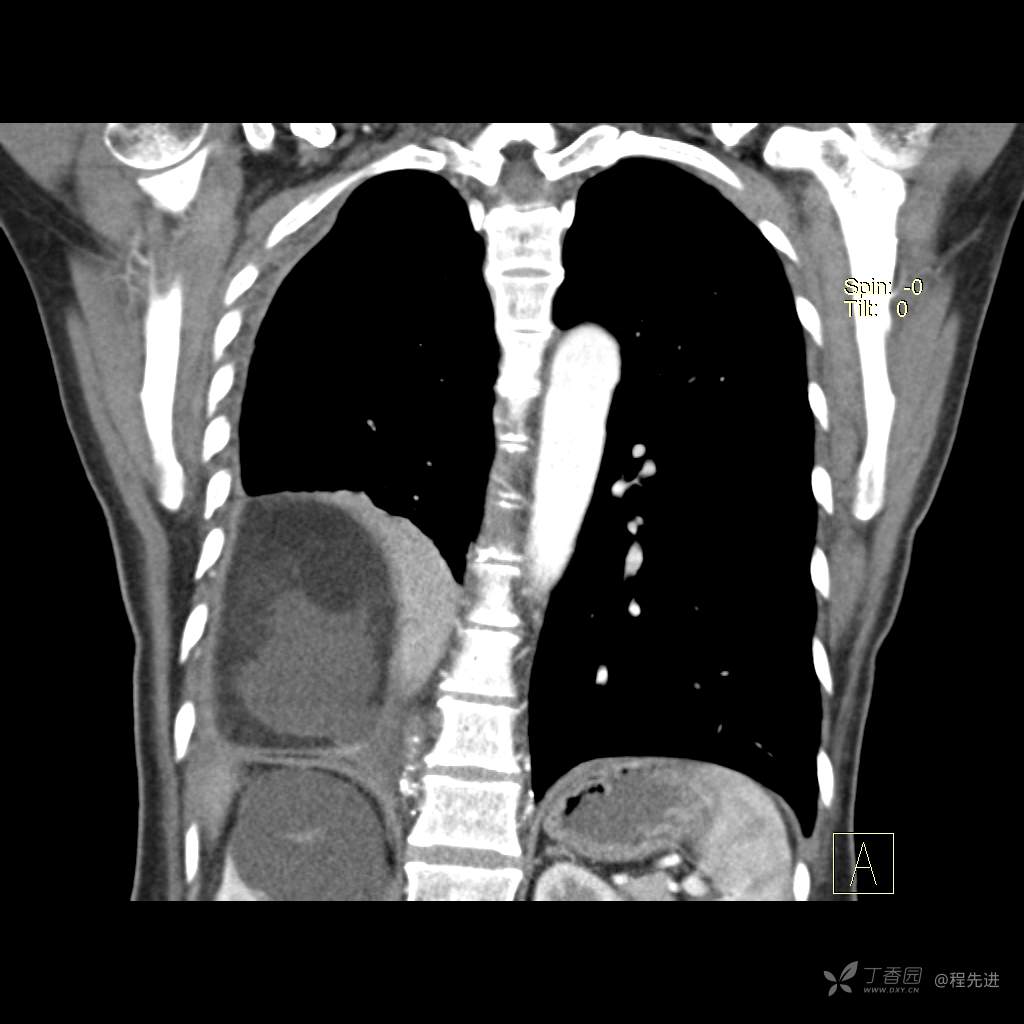

患者性别:女

患者年龄:51岁

简要病史:胸闷半年